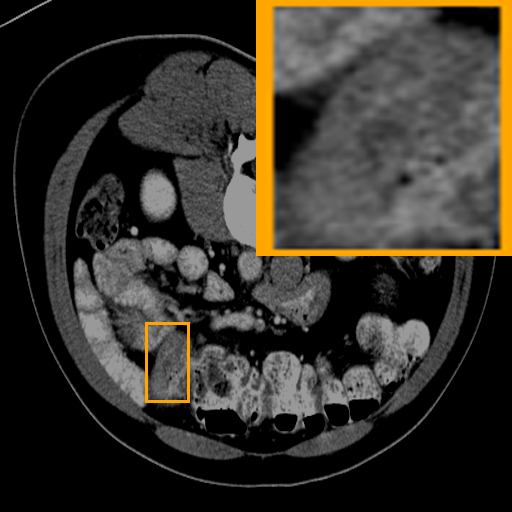

KiTS21-Case 58

Refer to caption

Pancreas-Case 200

LiTS17-Case 29

Colon-Case 9

(a) Image

(b) Ground Truth

(c) DEAP-3DSAM

(d) 3DSAM-Adapter

(e) UNETR++

(f) Swin-UNETR

(g) TransBTS

Figure 3: Qualitative comparison visualization of DEAP-3DSAM and baselines on four datasets.

IV-B2 Qualitative Performance Comparison

We also performed qualitative analysis on four datasets. As illustrated in Fig. 3, DEAP-3DSAM accurately identifies the target regions and closely matches their size. In contrast, 3DSAM-Adapter [3dsamadapter] exhibits limitations in matching the size and shape of the target regions. This proves that DEAP-3DSAM captures more complex image features, owing to its Dual Attention Prompter and Feature Enhanced Decoder. Furthermore, while these SAM-based methods are nearly capable of localizing the target regions, many traditional methods, i.e. UNETR++ [unetr++], Swin-UNETR [swinunetr], and TransBTS [transbts], struggle to achieve this. This highlights the potential of SAM-based methods for addressing complex 3D segmentation tasks.